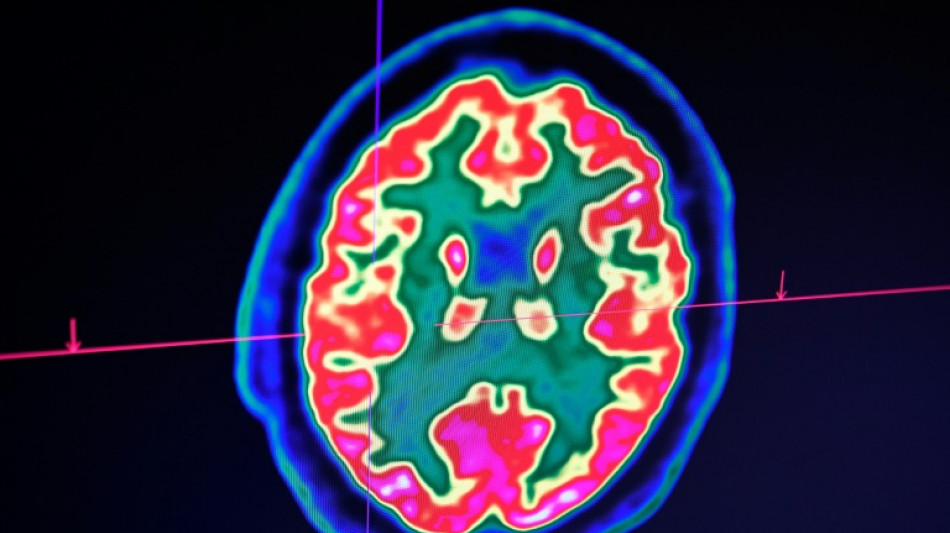

Cancer du cerveau: la guérison d'un enfant ouvre de grands espoirs pour la recherche

Cancer du cerveau: la guérison d'un enfant ouvre de grands espoirs pour la recherche / Photo: Fred TANNEAU - AFP

Rare mais fatal, le gliome infiltrant du tronc cérébral est l'une des formes les plus redoutables des cancers du cerveau pédiatriques. Un enfant, pourtant, semble défier les statistiques: sa guérison, unique au monde, suscite aujourd'hui de grands espoirs pour la recherche.

Inopérable, ce cancer est traité habituellement par une radiothérapie, qui permet parfois de freiner la maladie mais dont l'effet est transitoire. Aucun médicament n'a encore démontré son efficacité.

D'emblée, Lucas répond très bien au traitement. "Au fil des IRM, j'ai vu la tumeur complètement disparaître", raconte le Dr Grill, qui n'ose, malgré ces résultats miraculeux, décider d'arrêter le médicament. Jusqu'à ce qu'il comprenne, il y a un an et demi, que l'enfant avait lui-même cessé de le prendre.